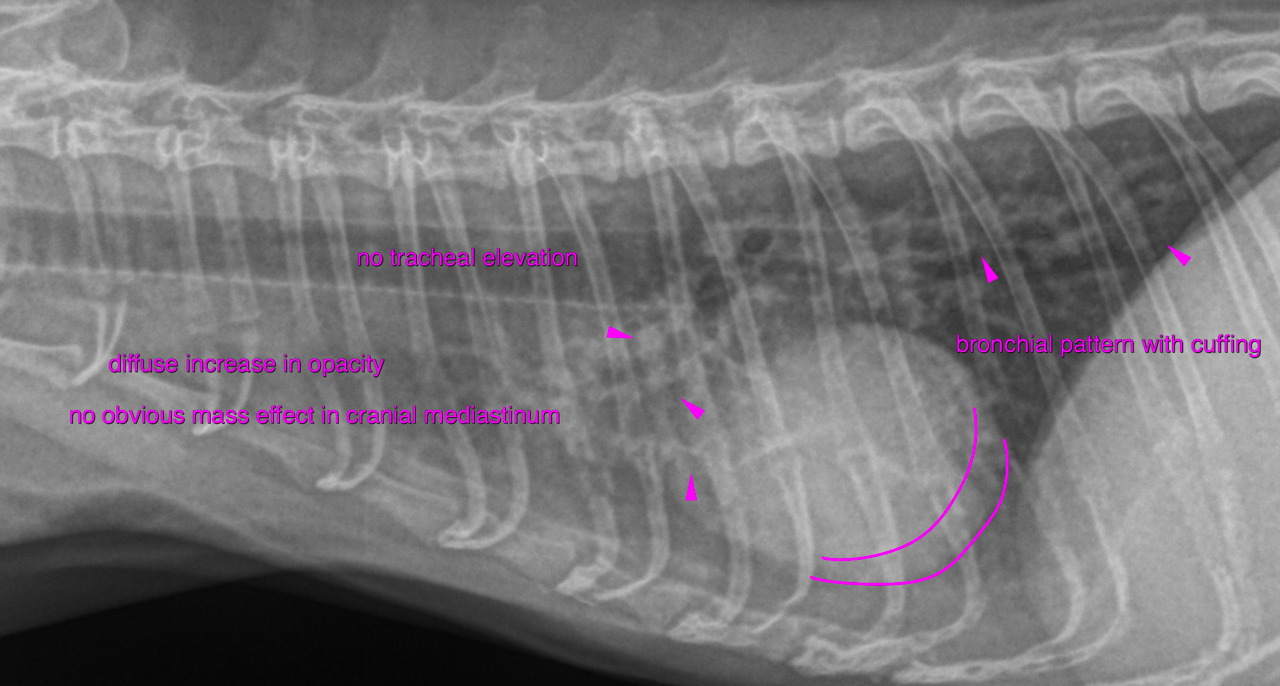

Rads of the thorax – A moderate multifocal bronchial pattern with peribronchial cuffing is noted.

The cranial mediastinum reveals widening at 2 times the width of the spine. The

cranial mediastinum and pericardium reveal double opacity contours indicative of

mediastinal fat. There is moderate generalized splenomegaly with rounded margins. The splenic head